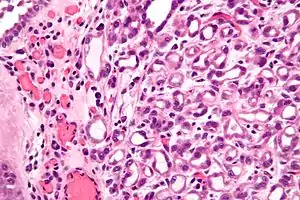

Micrograph of a nephrogenic adenoma. H&E stain.

Nephrogenic adenomas are diagnosed under the microscope by pathologists. Microscopically the tumor shows closely packed small tubular structures in edematous stroma. The tubules show considerable variation in size and shape resembling convoluted tubules of the kidney. The single layer of cells lining the tubules are cuboidal with a scant to moderate amount of cytoplasm. In some areas they may have a hobnail appearance. [2]